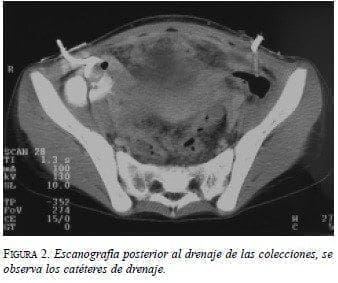

Como que la paciente se encontró en condiciones estables, sin evidencia de sepsis ni obstrucción intestinal y tolerancia de la vía oral, se inició antibioticoterapia con clindamicina y gentamicina con el propósito de controlar el proceso infeccioso, y soporte nutricional vía parenteral debido a que llevaba varios días con aporte proteico-calórico inadecuado. Además, bajo sedación y anestesia local se realizó un drenaje percutáneo guiado por escanografía con contraste endovenoso, con el cual se obtuvieron 1.000 cc de material purulento; se dejaron dos catéteres “cola de cerdo” para drenaje (figura 2). Inmediatamente después se trasladó a la paciente a la unidad de cuidado intensivo (UCI), ya que esperábamos una respuesta inflamatoria sistémica secundaria a la bacteremia provocada por la manipulación de las colecciones.

Los catéteres se lavaron periódicamente hasta que el drenaje fue mínimo; se realizó un control tomográfico que confirmó desaparición de las colecciones y se retiraron los catéteres después de cinco días.